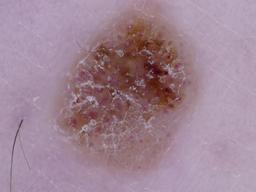

MILK10k consists of 10480 images, each representing a paired clinical close-up and dermatoscopic image for 5240 lesions. The dataset’s metadata include age (in 5-year intervals), sex, anatomic site, skin tone, diagnosis, method of ground truth establishment (histopathology or other means), and, if a dermatoscopic image of the same lesion was previously included in ISIC, its corresponding ISIC identifier. Skin tone is categorized into six levels, ranging from very dark (0) to very light (5), intentionally distinct from the Fitzpatrick skin types to avoid confusion. Most patients had skin tones in the middle ranges. Of the 5240 lesions, 95.7% were biopsied or excised, with histopathology serving as the gold standard for diagnosis. Diagnoses were mapped to both the ISIC-Dx diagnostic scheme and a simplified classification based on the ISIC2018/2019 challenge and HAM10000 diagnostic categories. The dataset includes 11 broad diagnostic categories:

- Basal cell carcinoma (bcc)

- Melanocytic nevus (nv)

- Benign keratinocytic lesion (bkl)

- Squamous cell carcinoma/keratoacanthoma (sccka)

- Melanoma (mel)

- Actinic keratosis/intraepidermal carcinoma (akiec)

- Dermatofibroma (df)

- Inflammatory and infectious conditions (inf)

- Vascular lesions and hemorrhage (vasc)

- Other benign proliferations including collision tumors (ben_oth)

- Other malignant proliferations including collision tumors (mal_oth)

Additionally, we provide the most specific ISIC-Dx diagnosis and its parent branch in the ISIC-Dx diagnostic tree. In cases where a dermatoscopic image of the same lesion was already included in the ISIC archive, its ISIC identifier is reported in the metadata. Furthermore, all images have been annotated using the MONET framework, with probabilities for the following concept term groups included in the metadata: